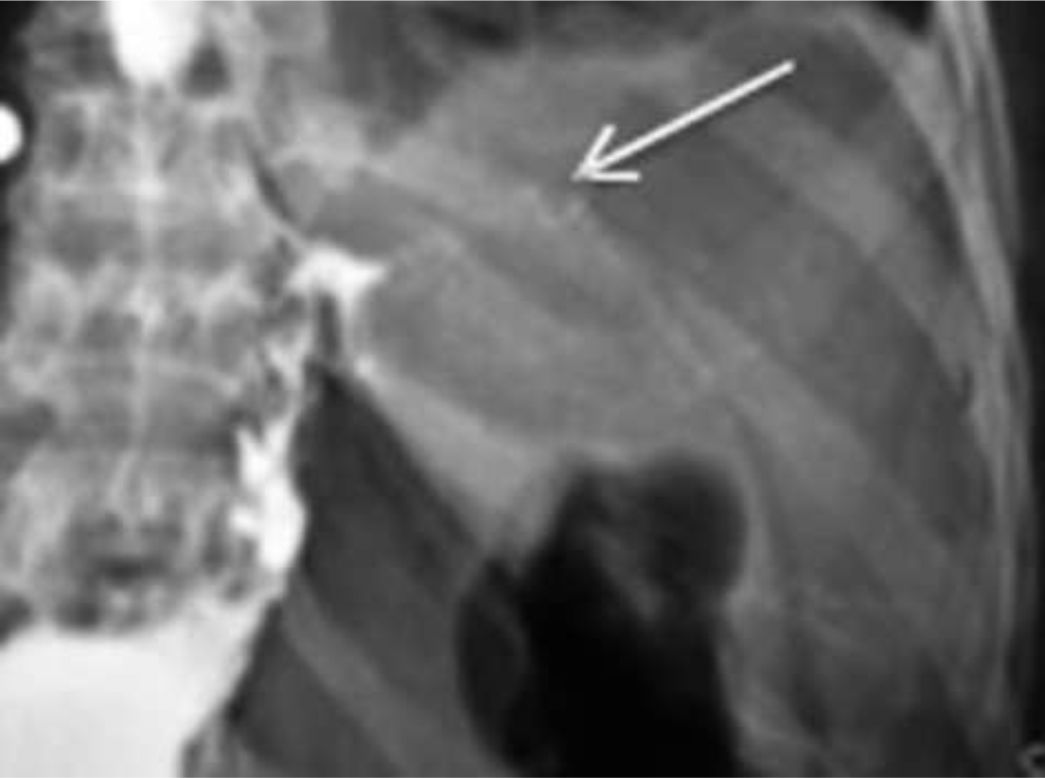

Figura 7

Paciente cursando postoperatorio mediato que comenzó con dolor abdominal y taquicardia.

a) Corte axial

b) Reconstrucción coronal de TC

con medio de contraste i/v, sin contraste oral observándose un absceso a nivel subfrénico izquierdo (flecha fina) y escaso derrame pleural del mismo lado (flecha gruesa)(Paciente Nº 6)

b) Colecciones y abscesos Las colecciones y los abscesos usualmente se producen como consecuencia de fugas. La TC con contraste i/v es el estudio de elección. Los abscesos se presentan como una lesión bien definida, hipodensa, es avascular, uni o multilocular (signo del acúmulo o cluster), con realce periférico y de los septos tras la administración del medio de contraste i/v. A veces contienen líquido, gas y/o niveles hidroaéreos, la presencia de contraste oral en su interior orienta a fístula. En general se topografían en el cuadrante superior izquierdo, más frecuentemente en el espacio subfrénico (6,7,10). FIGURA 7